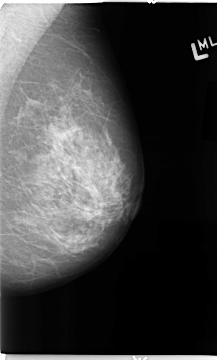

B_3116_1.LEFT_MLO

LEFT_MLO LINES 4672 PIXELS_PER_LINE 2816 BITS_PER_PIXEL 12 RESOLUTION 50 NON_OVERLAY